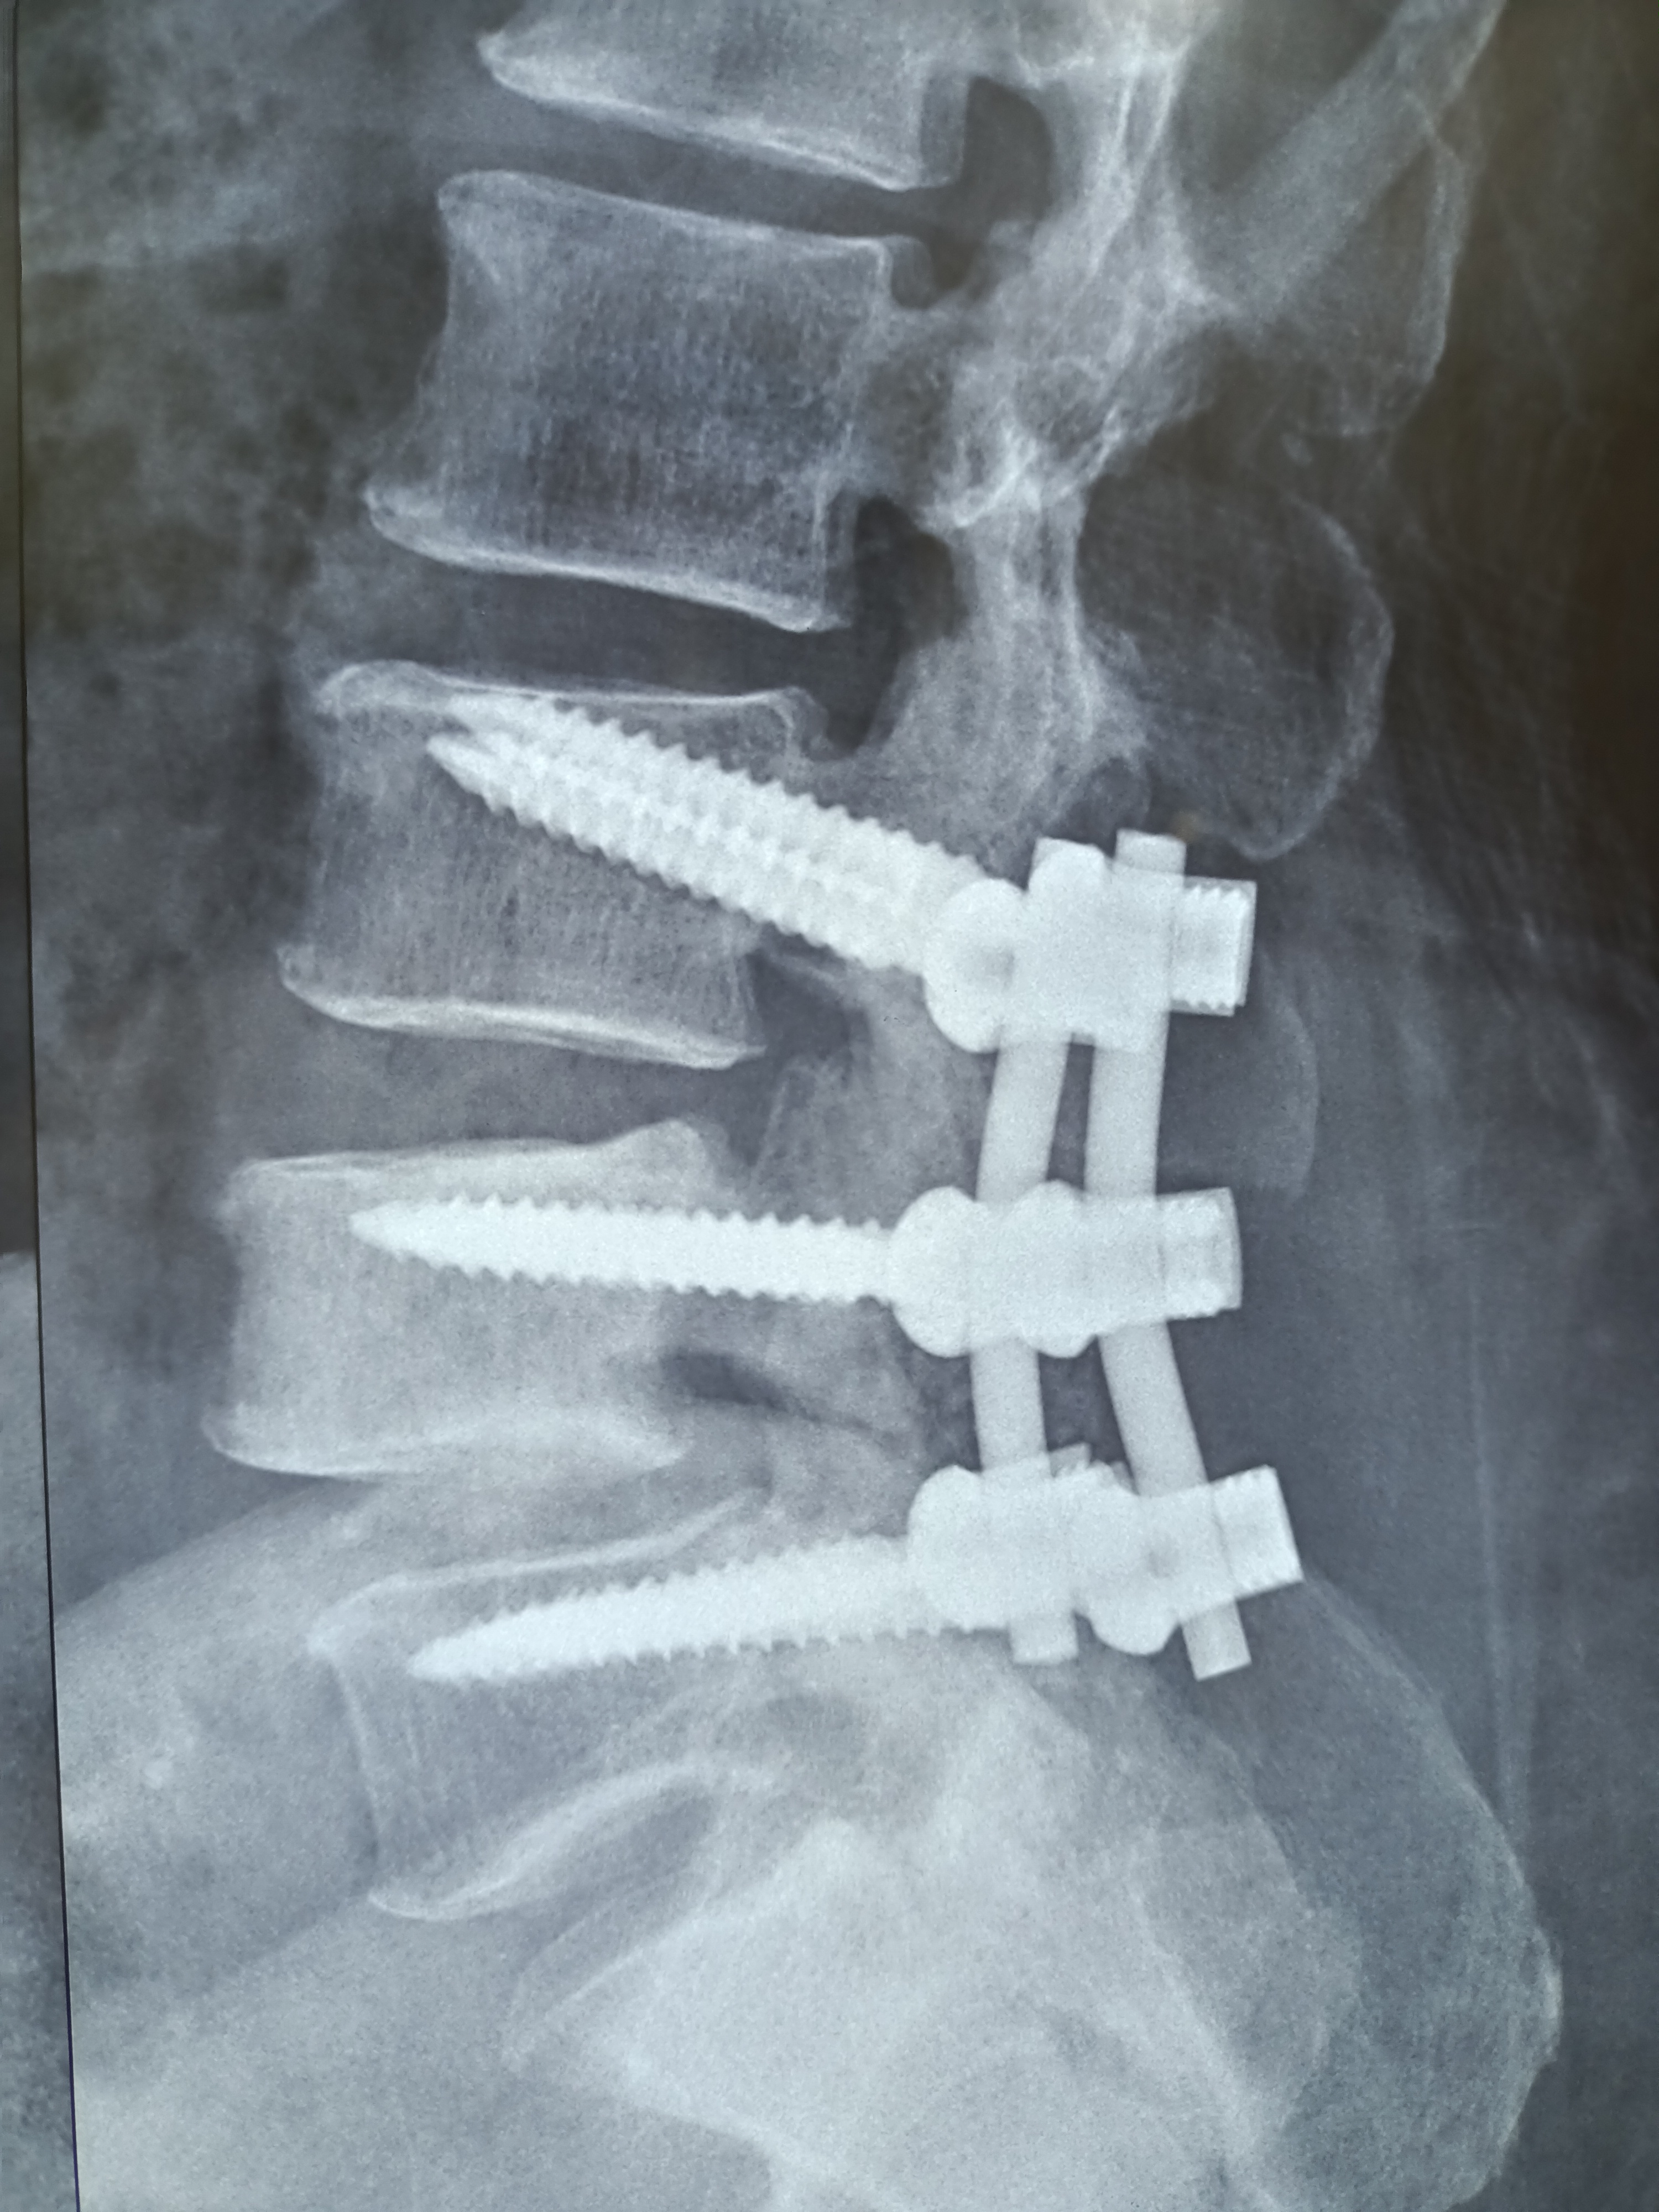

Lumar Canal Stenosis with Lumbar Spondylolisthesis - Decompression, Laminectomy and Pedicle screw fixation